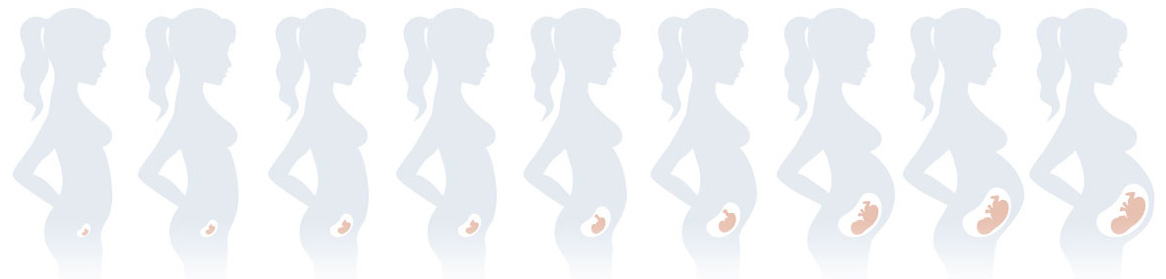

Pre-conception check helps you prepare yourself physically and mentally for pregnancy as well as parenthood. You can start with a detailed discussion with your Ob-gyn prior to conception. This helps you understand what to expect from pregnancy, see if there are any challenges to conception and have a better understanding of a parent-to-be.

For a wide range of reasons, several couples have difficulties in conceiving a child in the current generation. While this may not always be linked to fertility issues, lack of awareness, and other factors might be playing a role in the same. Thus, is highly advisable for couples to undergo a preconception counselling which not only helps conceive a child but also aids the planning required for a family.